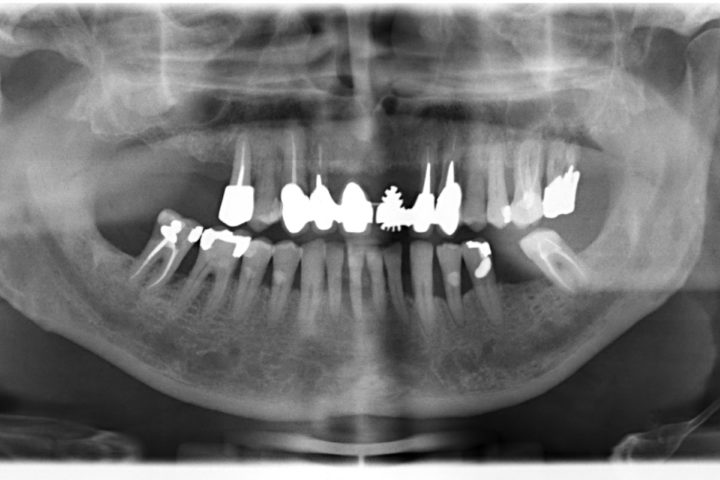

Arcata superiore - Fase iniziale, intermedia e finale